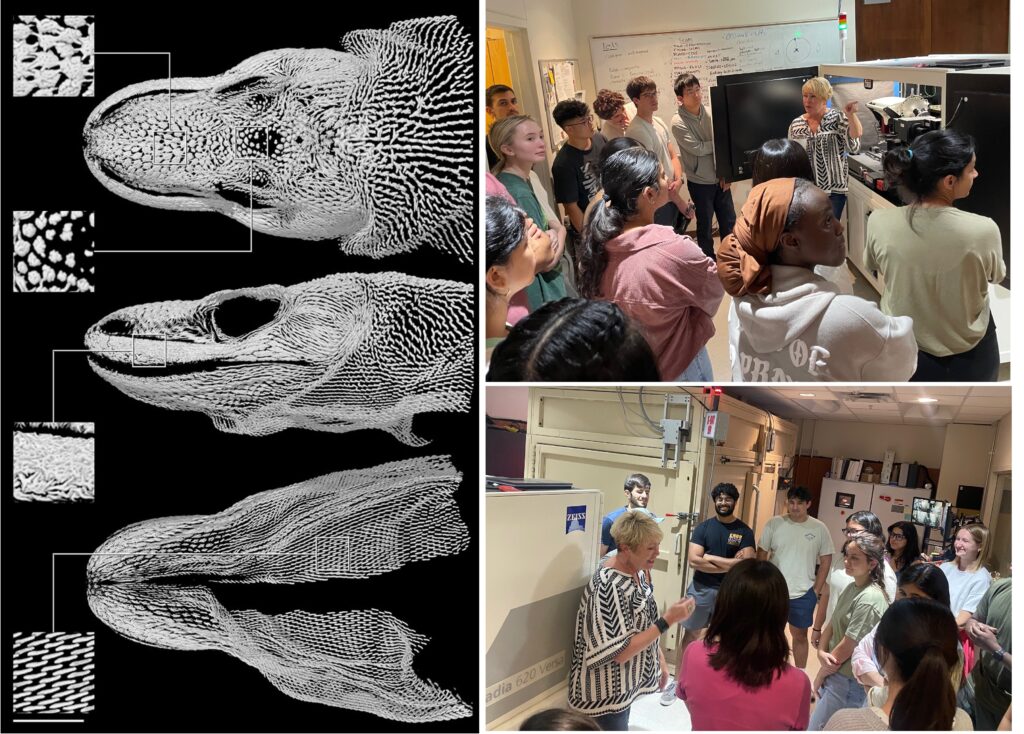

BME 357: Biomedical Imaging Modalities

Description: Exploration of the fundamental imaging modalities in “modern” radiology. In particular, we will introduce basic engineering, physics and physiological and clinical uses of X-ray radiography, computed tomography (CT), ultrasound (US), optical imaging, and magnetic resonance imaging (MRI). We will use homework, projects and hands imaging to reinforce and assess learning.

Pedagogy

Dr. Bush uses a problem and project-based approach to promote an active learning classroom. Classes combine fundamental concepts in medicine, physiology, physics and engineering with real world examples and uses of medical imaging.